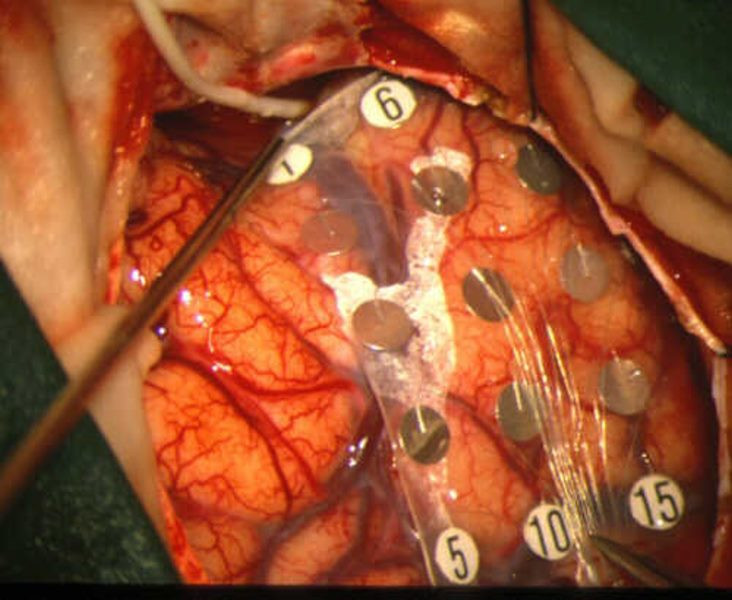

Galerias de Dr. Mauricio Ernesto Palacios Marchesini